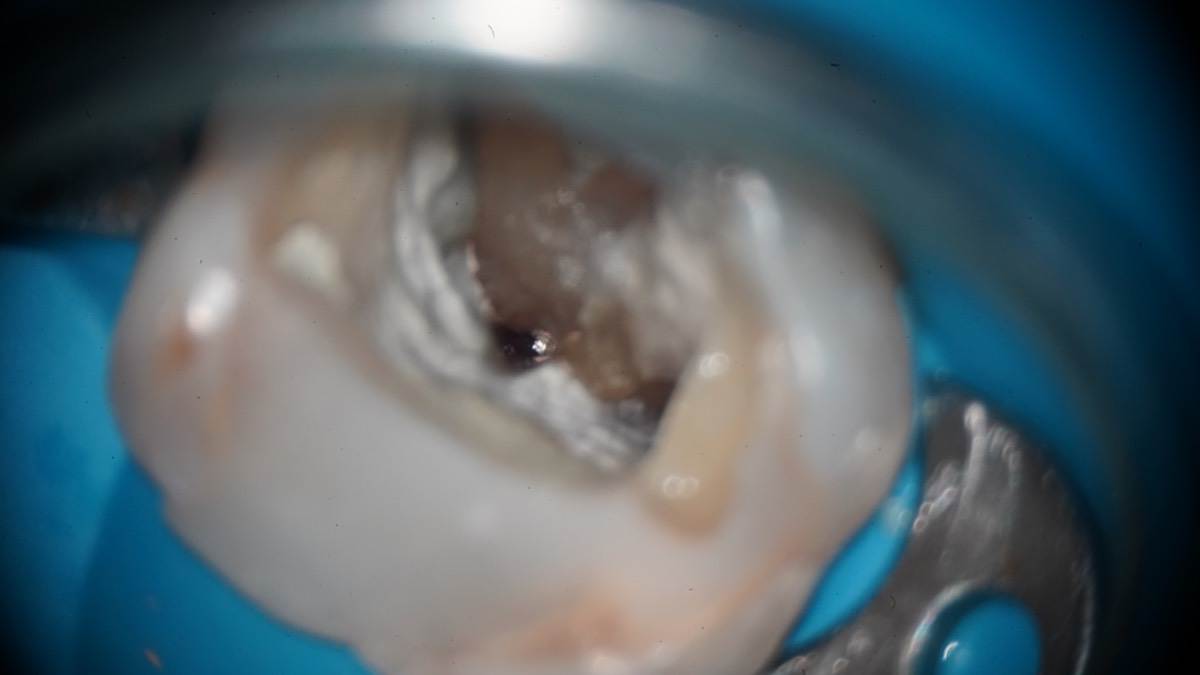

Гарриевич Опубликовано 7 апреля Автор Поделиться Опубликовано 7 апреля Извлечение двух фрагментов сломанных инструментов из одного зуба:) И если кому интересно, то вот полный фотопротокол 3 Ссылка на комментарий